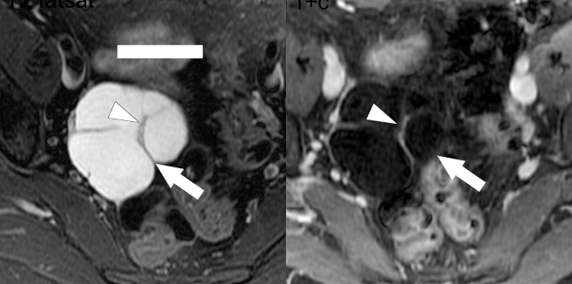

Optimizing images is just one hurdle for delivering the best imaging care to patients. Over the last decade, there has been a major movement toward standardized reporting for many disease processes in the abdomen and pelvis. Standardized reporting allows for more precise communication of results and improves compliance with diagnostic criteria. Notably, the liver imaging reporting and data system (LI-RADS), PI-RADS, ovarian reporting and data system (O-RADS), and updated Bosniak criteria are increasingly recognized as the standard of care for interpretation and reporting. ARRS Symposia course codirector Kathryn J. Fowler, Westphalen, Raman, and Sadowski provided an overview of these important systems, a framework for applying them, as well as insights into creating templates to improve reporting efficiency (Fig. 2).